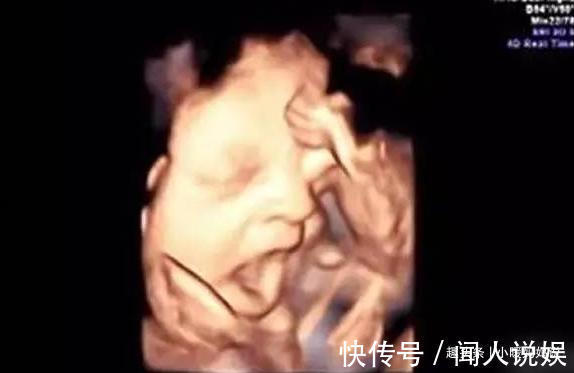

这天和往常一样来做产检,刚做检查没几分钟,医生当场就笑翻了,笑着对宝妈说:“你家孩子可太有趣了,我正检查呢,你猜他干什么呢?”宝妈一脸迷茫,“他干什么了?”医生哈哈大笑几声说:“你家孩子居然在尿尿,你快看!”医生说完,宝妈转头看屏幕,竟然是在尿尿,这个动作让宝妈觉得尴尬极了,心里想:小样的,你还没出生呢,就让我这么尴尬,等你出生看老娘怎么收拾你。

3. 搞小动作宝妈经常能看见,在做四维的时候,孩子居然在做鬼脸,好像在和妈妈玩游戏,有的会嘟嘴,还有的会吐一吐舌头,也有的小宝宝还会笑,也有的很淘气,总是不让你看见正脸,好像出生的时候给你一个惊喜,宝妈们的心都要融化了。小宝宝还会吮吸手指,将手指伸进嘴里,小嘴有一下没一下的吮吸,小肚子还会跟着上下蠕动,简直太可爱了,妈妈是不是更加期待了?